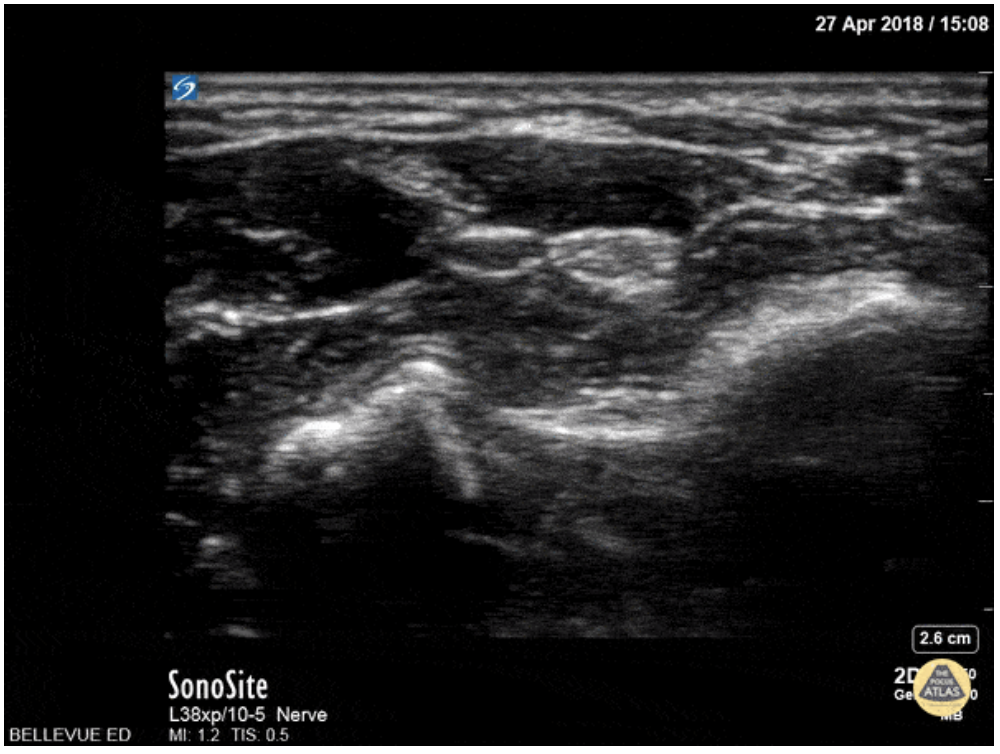

Ultrasound guidance is preferred given the ability to visualize the desired nerve and proper instillation of the anesthetic around the nerve. On ultrasound nerves are circular or triangular hyperechoic structures with hypoechoic structures within. Often described as having a “honeycomb” appearance as seen in the image of the median nerve below.